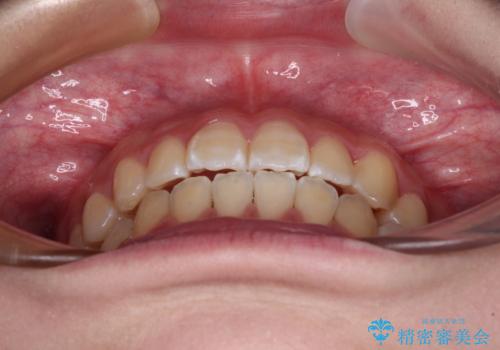

- 前歯のデコボコと磨きにくい奥歯を気にして来院された患者様です。

左右ともに上顎第二大臼歯が外側に転位しており、大変磨きにくくなっているため、補助装置により内側に引き込むことで改善することとしました。

外側を向いていた奥歯は比較的早い時期に歯列に収まり、咬み合わせも磨きやすさも改善することができました。

歯列は元々悪くなかったので、1年ほどで治療を終えることができました。